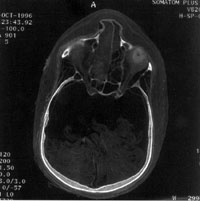

Tomografía computarizada del cráneo

de una momia del 900 a.C

Los rayos X y la tomografía computarizada, que pueden ser realizadas sin quitar los vendajes de la momia e incluso sin abrir el sarcófago han sido una valiosa fuente de información, mostrando las estructuras óseas, tejidos blandos e implantes. Las cavidades corporales pueden ser exploradas por endoscopia practicando sólo pequeños orificios para la introducción de la fibra óptica.